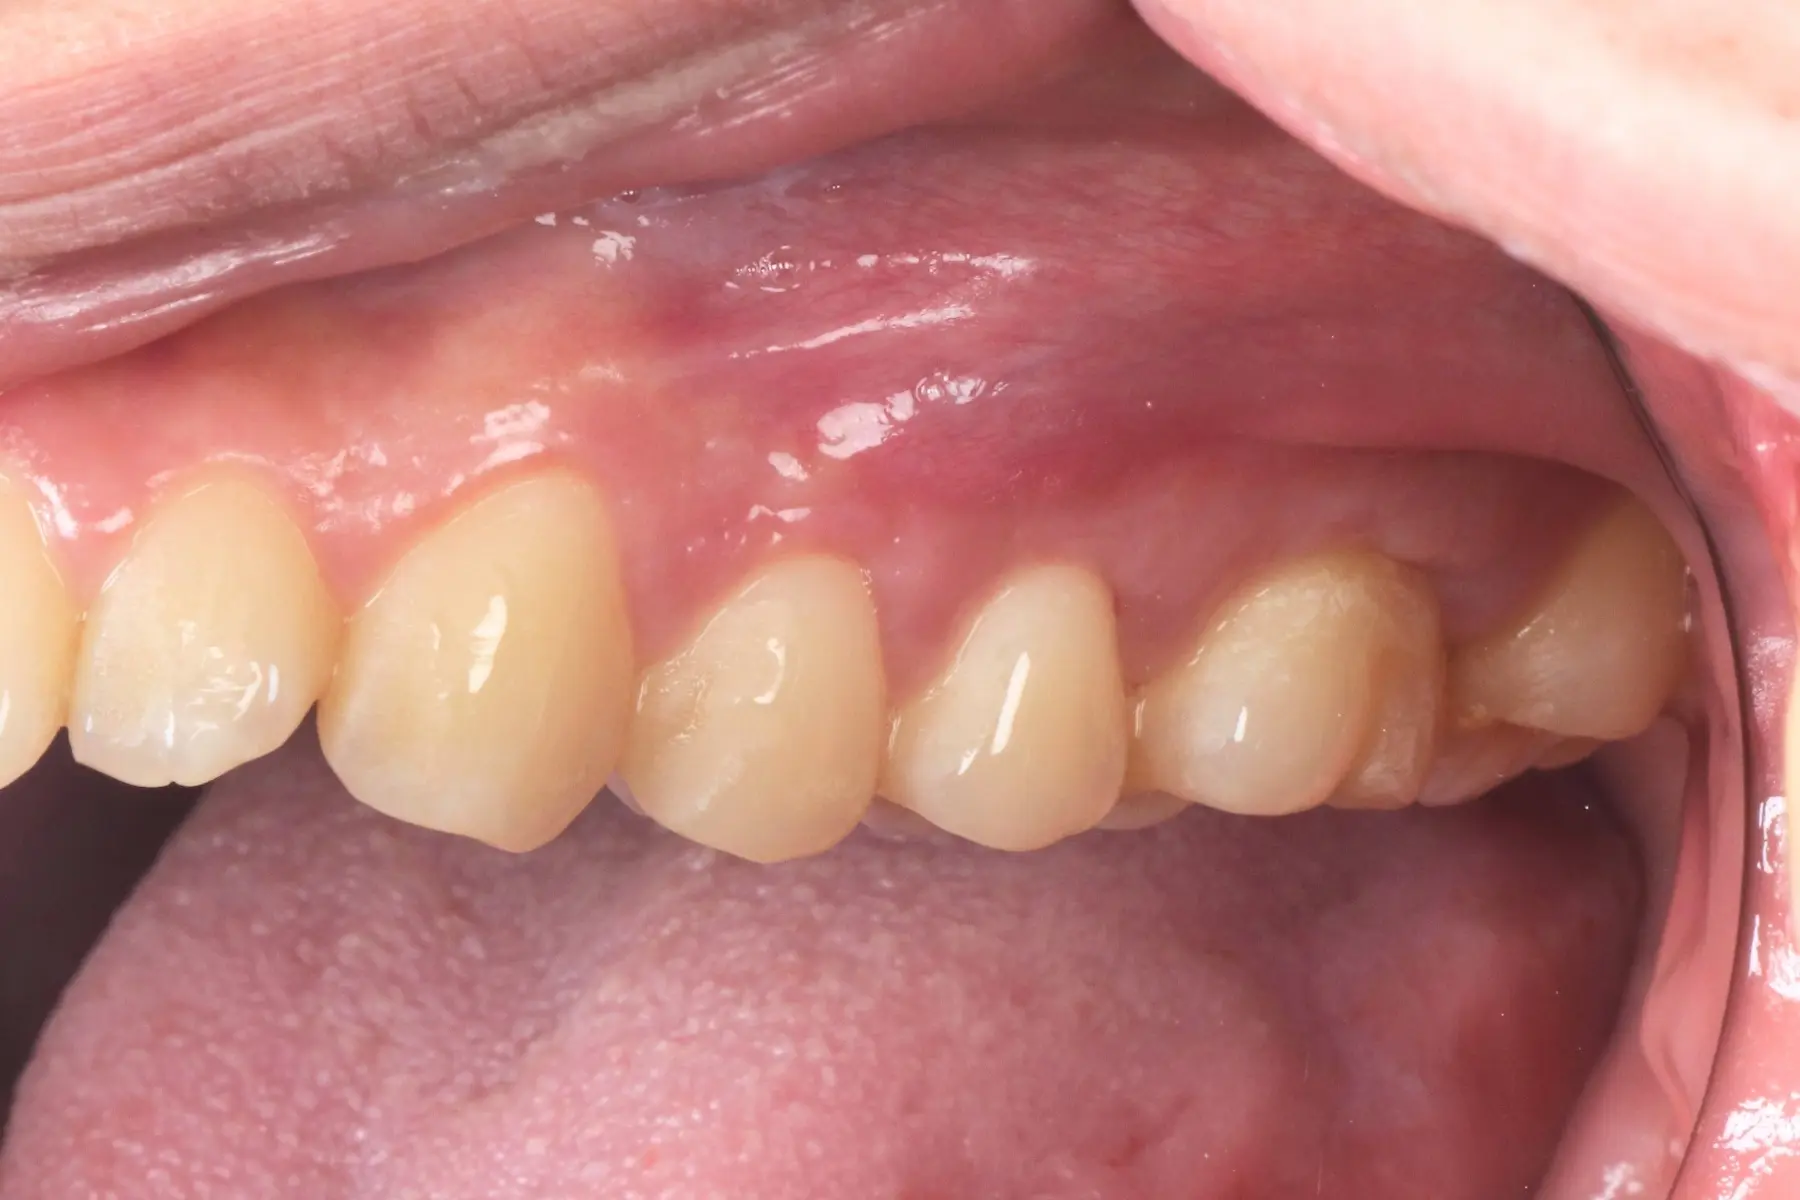

牙周治療

主治醫師

• 鍾國耀

治療時間

三次療程

主訴

右上前牙牙齦反覆腫脹化膿